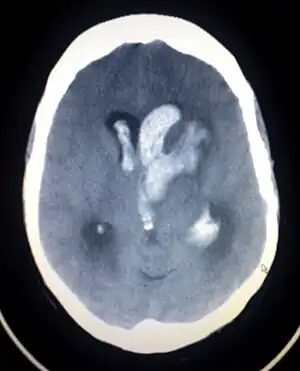

| Axial CT scan of a spontaneous intracranial hemorrhage | |

CT scan (computed tomography) of the brain (without any iodinated contrast), is the initial imaging choice because of its high speed, good accessibility in hospitals, high sensitivity in detecting brain injuries or brain diseases, thus helping to triage patients in emergency department in a timely manner and urgent neurosurgical intervention can be administered. Examples of brain diseases that require urgent intervention are: large volume hemorrhage, brain herniation, and cerebral infarction. Other advantages of CT over MRI scan are ability to detect bony fractures, vascular injury, and cerebrospinal fluid (CSF) leak. It also does not need to screen for MRI safety of implants/foreign body especially for penetrating or blast injuries.[4] Moreover, CT scans have also been used to train deep learning models to automatically perform intracranial hemorrhage detection.[5] Interestingly, deep learning models have been found to reach expert-level performance.[6][7]